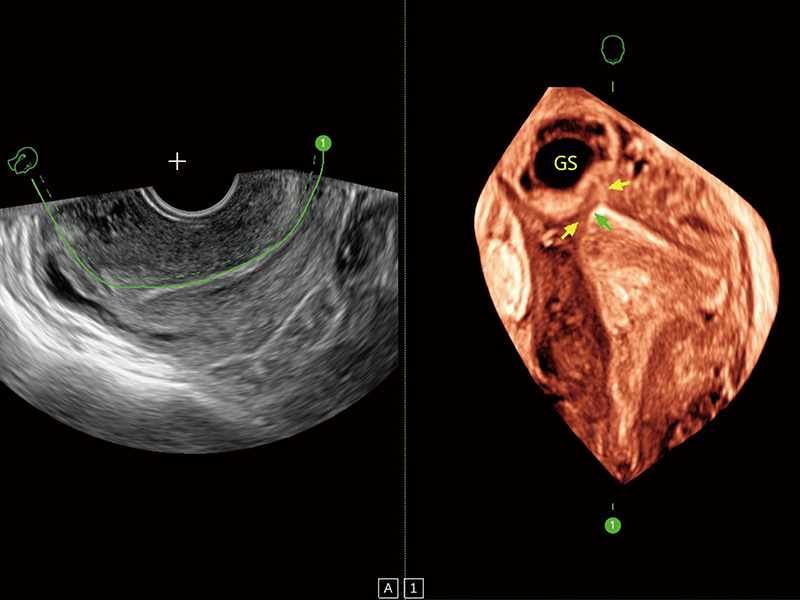

卵巢多囊样改变

超声引导下胚胎移植